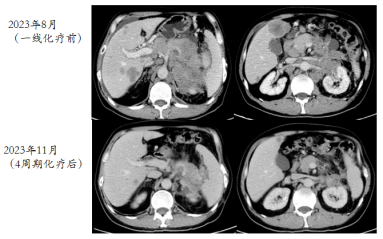

2023-08-29胸部CT未见转移,腹部CT:结肠脾曲术后,肝多发转移,胰腺区,肾前,脾内侧多发转移,病变包绕胰腺及脾动脉静脉,胃底及左上腹静脉迂曲扩张,肝门区,肠系膜内及腹膜后,左侧髂血管旁周围多发肿大淋巴结。左肾周受侵。

image.png

图1 2023年8月29日检查结果

(2023年11月)4周期化疗后,复查CT评效:肝多发转移,较前减少缩小,胰腺区,左肾前,脾内侧多发转移较前明显缩小,肝门区,肠系膜内及腹膜后淋巴结较前明显缩小,部分消失。评效部分缓解(PR)。

图2 4周期化疗后复查CT结果